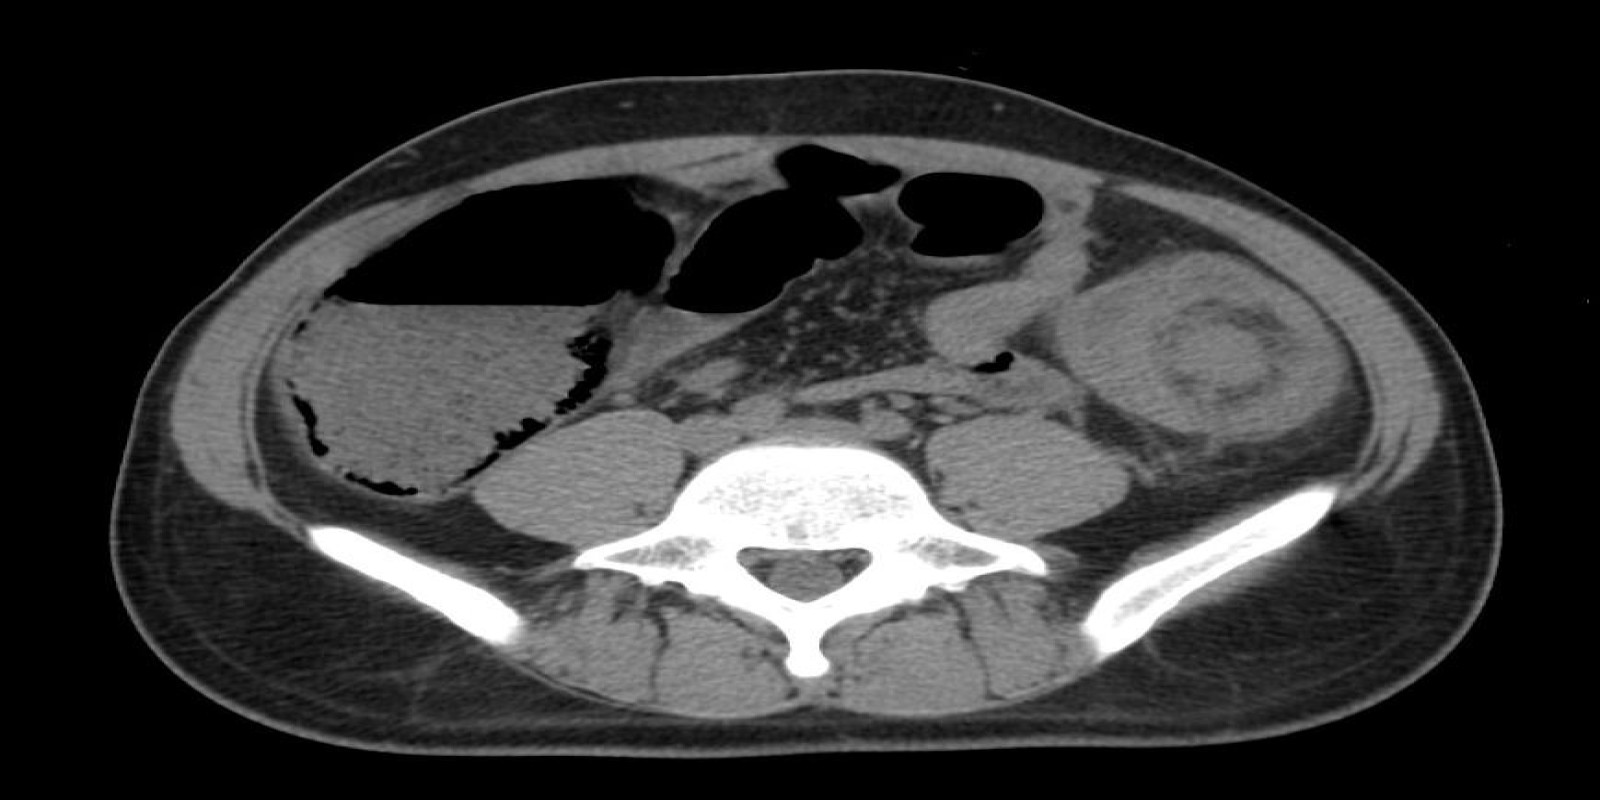

Caso Código 267A de Intussuscepção

Cod.: 267A